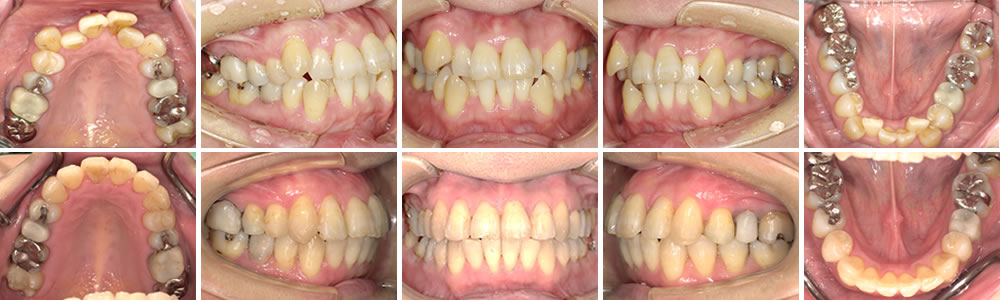

叢生・八重歯の矯正治療例(40代女性 1年9ヵ月)

叢生・八重歯の治療例(Before&After)と解説

上段が初診時の口腔内写真となります。上下顎ともに著しい叢生が認められ、正中のズレも認められます。ディスクリパンシー(顎骨と歯列の大きさの不一致)が大きく、抜歯の対象となり得るケースですが、本人の抜歯をしたくないという強い希望により、非抜歯での治療となりました。

上顎にはゴムメタルを使用した固定式拡大装置を用いて積極的に拡大を行いました。下顎には0.36インチのゴムメタルワイヤーを用いたオーバーレイアーチを装着して歯列拡大を行いました。

通常通りニッケルチタンワイヤーにてレベリング(歯列の平坦化)を行いました。

その後、0.18×0.22インチゴムメタルワイヤーを使用して確実な歯体移動(歯を傾斜することなく平行に移動させる)と歯列拡大を継続します。

1年9ヵ月の治療期間で下段の写真のとおり終了となりました。